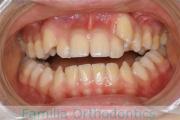

上の出っ歯、口が閉じにくい、下の前歯のガタガタを治したいということで来院されました。上顎から左右小臼歯を、下の前歯は凹凸が非常に強いので、こちらから一本抜歯を行いました。2年強、30回程度の通院が必要でした。

成人になってからの叢生(でこぼこ、凹凸、ガタガタ)は、保定をしっかりしないと後戻りをしてしまうリスクが高いです。

- ≫治療前

-

上顎

下顎

前歯の関係など

右側

正面

左側

- ≫治療後